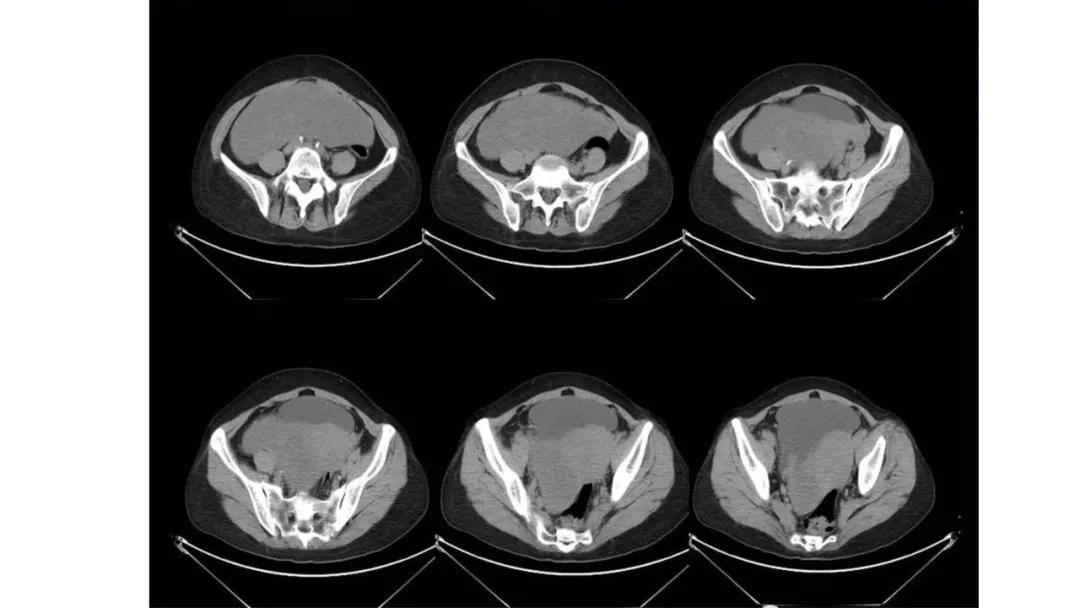

病例4 女,32岁,以“月经量增多伴经期延长半年。”

缘于患者入院前半年无明显诱因出现月经量增多,卫生巾由原来3包余增至5包不等,伴血块,经期由原来7天延长至10-15天不等,无痛经,无月经周期改变,无阴道异常排液,无畏冷、发热,无头晕、乏力等不适,未重视,未诊治。期间症状持续。2月前就诊我院,查彩超示:“子宫体大小约5.7*5.3*4.6cm,内膜厚约0.6cm,回声不均,左卵巢旁探及大小约4.2*3.5cm低回声区。”建议治疗,患者及家属表示考虑。期间症状持续,今就诊我科门诊,要求住院手术治疗,无腹痛等不适,门诊拟“卵巢囊肿”收住入院。既往史:2007年剖宫产一次,术顺。月经史:15 7/25 lmp2018.05.14,量中,无痛经。婚育史:已婚,1-0-3-1,末孕2007年剖宫产娩一男婴,儿子及丈夫体健。个人史、家族史均无特殊。

CA125 335.5(U/mL);2018-05-30 彩超:子宫宫体大小约5.6㎝×6.3㎝×4.9㎝,形态正常,宫壁回声欠均,内膜厚约1.8cm,回声不均。CDFI:子宫内未见明显异常彩色血流信号。左附件区探及一混合回声团块,大小约9.8㎝×7.9㎝,CDFI:其实性部分可见少许彩色血流信号。右附件区未见明显包块回声。

病理:卵巢子宫内膜样癌